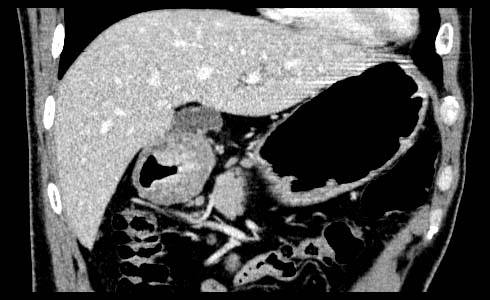

Gastric cancer / Borr.II

Coronal MPR

Data acquired & processed by R. Kato M.D.